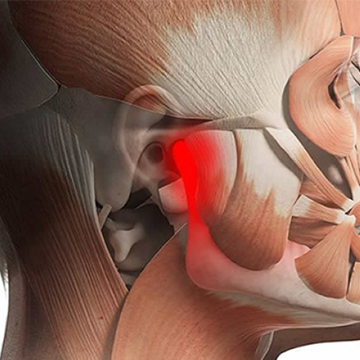

Temporomandibular Eklem (TME), alt çene kemiğini kafatasına bağlayan aynı zamanda, kayan bir menteşe gibi hareket eden bir eklem türüdür. Çenelerimizin her iki tarafında sağ ve sol tarafda birer adet olmak üzere iki adet çene eklemimiz bulunmaktadır.

Hastalarda TME hastalıklarının kesin nedenini teşhis etmek genellikle zordur. Ağrı; genetik, artrit (eklem iltihabı) veya çene yaralanması gibi faktörlerin bir kombinasyonundan kaynaklanıyor olabilir.

Çene ağrısı olan bazı hastalar dişlerini sıkma veya gıcırdatma (bruksizm) eğiliminde olsalar da tam tersi durumunda yani diş sıkan ya da gıcırdatan her hastada TME hastalıkları bulunmayabilir.

TME hastalıklarının riskini artırabilecek faktörler:

- Romatoid Artrit ve Osteoartrit gibi çeşitli artrit ( romatizma ) türleri

- Çene yaralanması

- Uzun süreli (kronik) diş gıcırdatma veya sıkma (Bruksizm)

- Temporomandibular Eklemi etkileyen bazı bağ dokusu hastalıkları

- Eklem hastalıklarının teşhisi klinik ve radyolojik muayene ile yapılır.

- Klinik muayenede; ağız içi ve ağız dışı olarak detaylı şekilde kas eklem çene muayenesi yapılır. Çenelere ’de hareket kısıtlılığı incelenir. Palpasyon ( parmak ile muayene ) kulak içinden muayene yapılır.

- Radyolojik muayenede; dişler ve çene kemiklerini incelemek için geleneksel çene röntgeni ( panoromik röntgen ),

- Eklemde yer alan kemiklerin ayrıntılı görüntülerini sağlamak için BT (bilgisayarlı tomografi) taraması,

- Eklem diski veya çevresindeki yumuşak doku (kas ve ligamentler) ile ilgili sorunları teşhis etmek için MRG ( emar ) incelemesi yapılır.